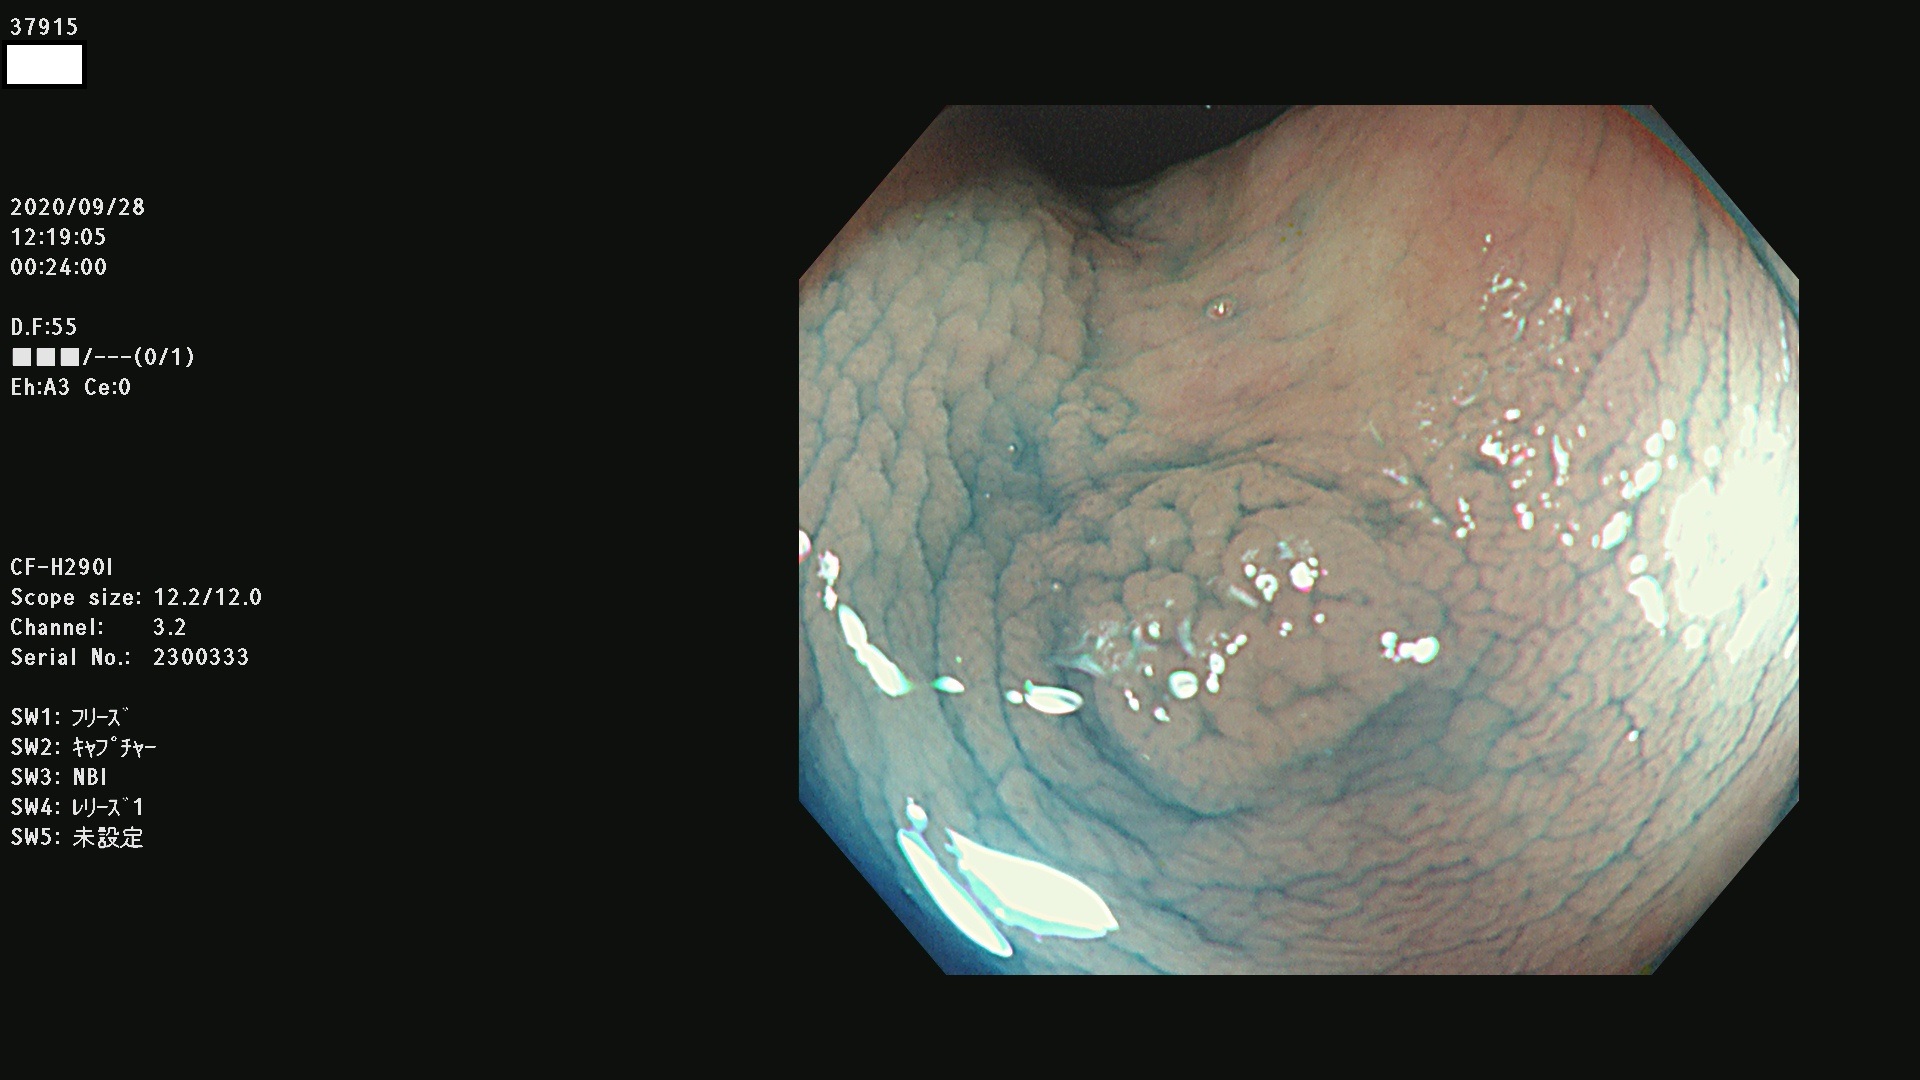

発見困難で危険性の高い平坦型病変(上記100名より抽出)

37900 37902 37903 37904 37905 37906 37907 37909 37910 37911 37912 37913 37914 37915 37916 37917 37919 37921 37922 37923 37926 37928 37929 37930 37931 37933 37934 37935 37936 37937 37938(SSAPのみ) 37939 37940 37941 37942 37943 37946 37947 37948 37949 37951 37952 37953(SSAPのみ) 37955 37956 37957(SSAPのみ) 37958(SSAPのみ) 37960 37962 37963 37964 37966 37967 37968 37971 37972 37973 37975 37976 37977 37979 37982 37983 37984 37985 37986 37987 37988 37989 37990 37991 37992 37993 37994 37995 37996 37998 37999